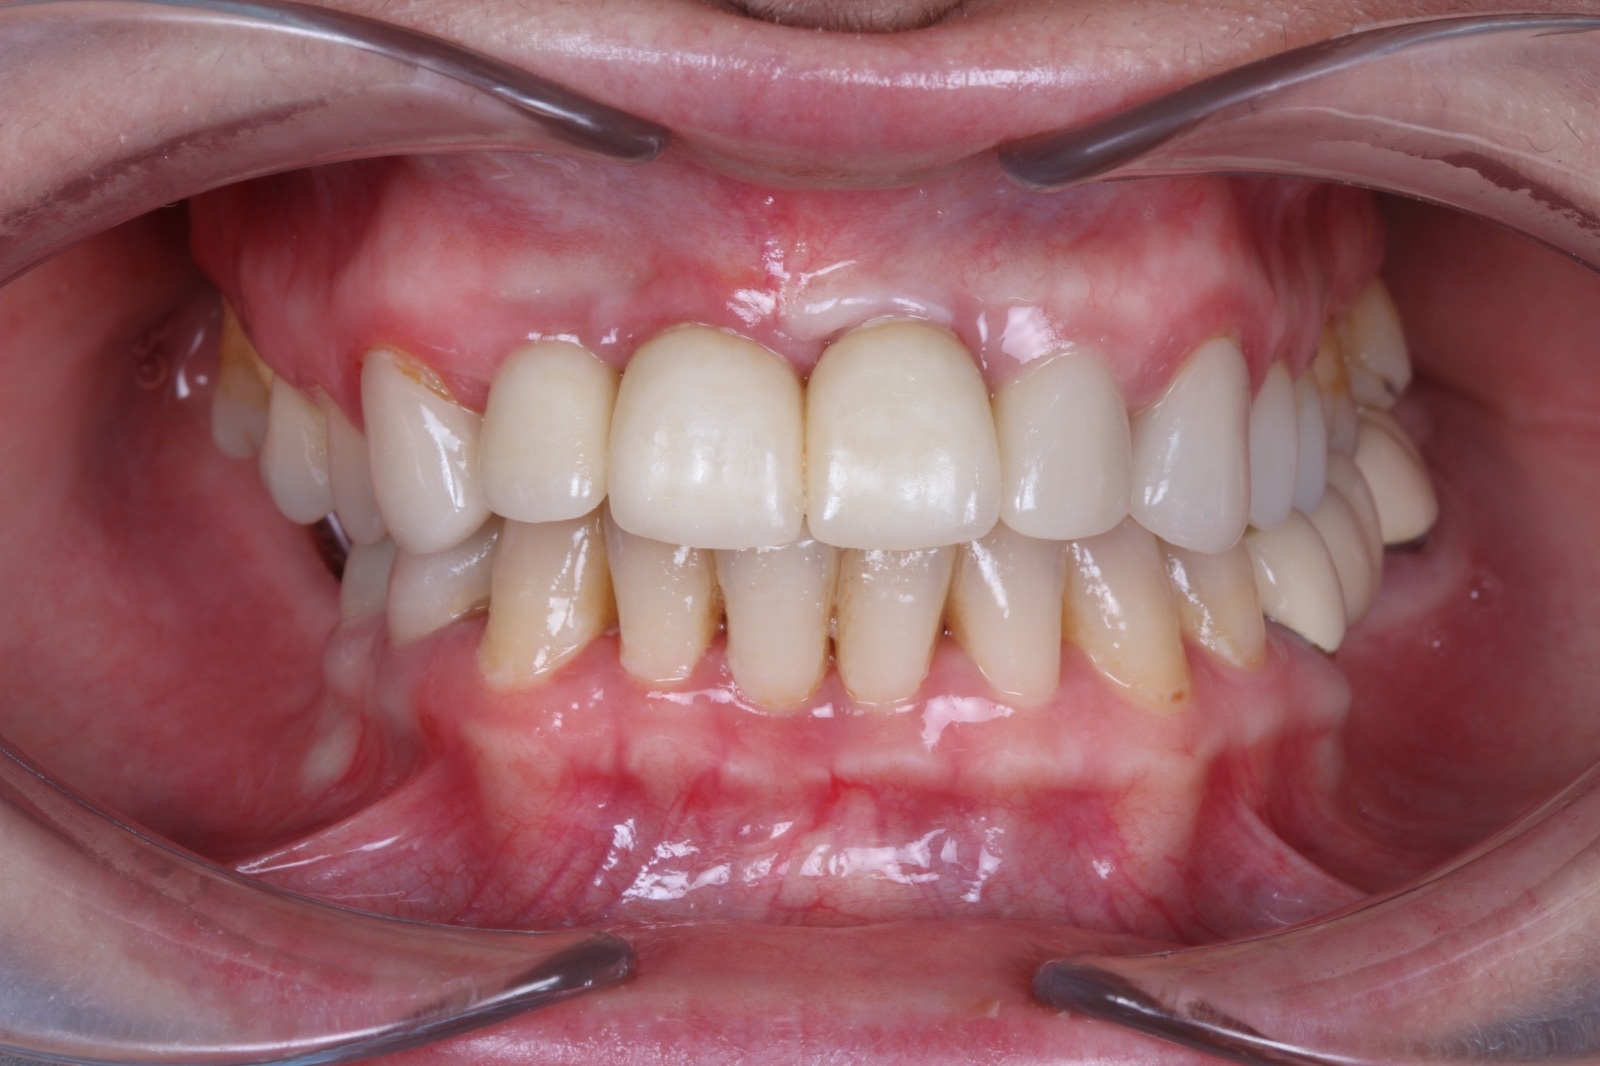

На временных коронка проверена высота прикуса и окклюзия.

Установлены коронки из оксида циркония с опорой на импланты и керамические виниры на нижних фронтальных зубах.